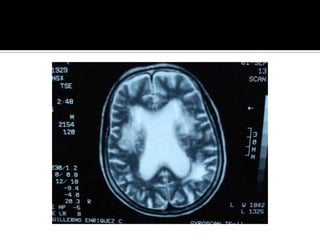

Pregunta 1¿ La lesion    cerebral es causada por una EVC de tipo isquemico o hemorragico o por una entidad no vascular?Respuesta: clinica  y Tomografia computarizada de craneo simple o RM craneal simple

Pregunta 1¿ Lalesion cerebral es causada por una EVC de tipo isquemico o hemorragico o por una entidad no vascular?Respuesta: clinica y Tomografia computarizada de craneo simple o RM craneal simple

¿Pregunta 2?¿Cual es la localizacion y magnitud de la lesion?Respuesta: TAC o RM

¿Pregunta 2?¿Cual esla localizacion y magnitud de la lesion?Respuesta: TAC o RM

Pregunta 3¿Cuál es la naturaleza ,localizacion, y gravedad de la lesion?Respuesta: clinica y Neuroimagen

Pregunta 3¿Cuál esla naturaleza ,localizacion, y gravedad de la lesion?Respuesta: clinica y Neuroimagen

Signos tempranos:  TAC en EVC AgudoSigno dela arteria cerebral media hiperdensaAtenuacion del nucleo lenticularHipodensidad cortical o subcorticalEdema cerebralBorrado de la region insularBorrado de surcos corticalesCompresion ventricularAtenuacion de contraste cortico-medular